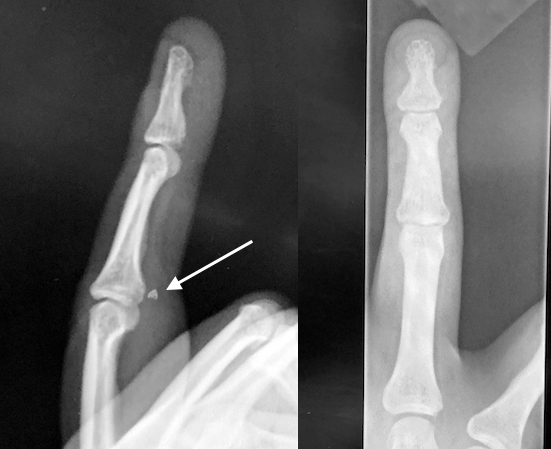

• X-ray of ringer finger jersey finger injury with avulsion fracture fragment (arrow) caught at the level of  PIP vincula and chiasma of Camper

X-ray of ringer finger jersey finger injury with avulsion fracture fragment (arrow) caught at the level of PIP vincula and chiasma of Camper